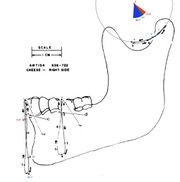

| 15:43, 13 October 2024 | Figure 1 (Accornero) copia.jpg (file) |  |

515 KB | Gianni | 1 | |